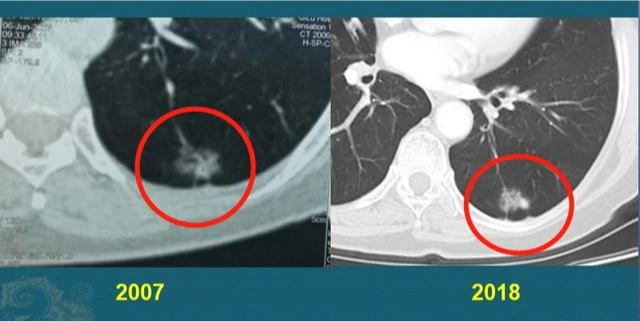

有些肿瘤属于惰性病灶(这种较量 少见),癌细胞在较长一段时期内呈惰性希望 ,像动物蛰伏一样,甚至十几年保持靠近 静止的状态。好比下面这个肺腺癌病例:

这位中年女士,体检发现左侧肺腺癌,体现为混淆磨玻璃结节,形态不规则,伴有胸膜牵拉,肺门侧可见一支供血血管。她对手术很是恐惧,选择亲近 视察,很幸运,她的这个病灶很是懒,一直到11年后才发现增大迹象,体现为密度增添 ,着实 不敢再拖了,最终手术切除,治愈!